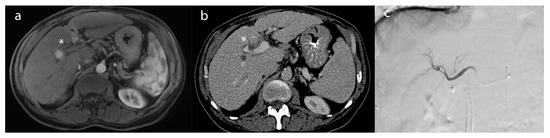

Figure 2. A 55-year-old male patient with (a) a lesion in segment 6 biopsy–proven as hepatocellular carcinoma (*)—on post-contrast T1-weighted imaging. (b) After microwave ablation, the lesion (*) demonstrated a lack of enhancement compatible with a complete radiographic response on the 1-month follow-up MRI (c) intraprocedural treatment CT of microwave ablation.

Ablative therapies include different procedures, such as percutaneous ethanol injection (PEI), radiofrequency ablation (RFA), microwave ablation (MWA), and cryoablation [3,4]. However, the goal of thermal ablation is to use heat extremes to induce tumor death through coagulative necrosis, eliminating undetected cancer microenvironments [37]. The procedure can be performed under moderate sedation or general anesthesia, and it involves the use of a percutaneous probe that navigates to the region of the tumor under CT or MRI guidance. In the context of RFA, the probe delivers frictional high-frequency alternating current to the target tissue, generating heat and, ultimately, the coagulative necrosis of the tumor. Temperatures (50–100 °C) produced by RFA denature proteins, disrupt cellular membranes, and induce thermal coagulation, leading to tumor cell death(Figure 2) [37,38]. After the procedure, patients are usually monitored through multiphasic CT or magnetic resonance imaging (MRI) to evaluate imaging response (Figure 2b). This assessment is typically done 1 month after the procedure. RFA has gained recognition as a well-established therapeutic approach due to its effectiveness, reproducibility, minimal incidence of complications, and widespread accessibility [39]. MVA, which employs electromagnetic energy to induce tumor cell injury, can also be particularly advantageous for liver tumors, due to its enhanced and predictable convection profile, sustained higher intratumoral temperatures, quicker ablation durations, and feasibility of treating multiple lesions, concurrently, using multiple probes [39,40,41].